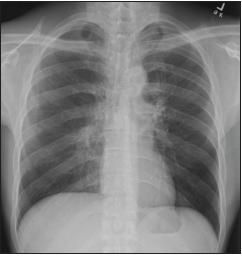

The patient was admitted to the neurosurgical service for brain biopsy. Treatment with dexamethasone was started for CNS edema. ACXR demonstrated a bilateral reticulonodular pattern with upper zone predominance and bilateral hilar predominance (Figure 3). A CT scan of the chest revealed multiple clusters of micronodular opacities in the upper lobes bilaterally and a large area of nodularity with architectural distortion and traction bronchiectasis in the left upper lobe (Figure 4).

Figure 3

This chest radiographshows a bilateral reticulonodularpattern with upper zonepredominance and bilateral hilarpredominance.